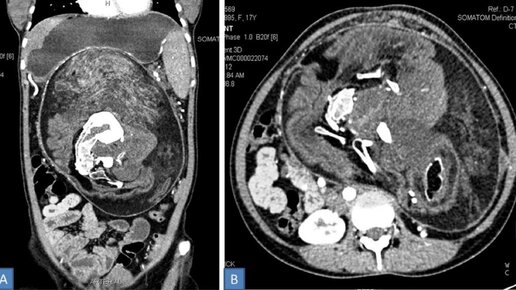

Эмбрион в эмбрионе: 17 лет девушка жила с "близнецом" внутри себя

В течение почти двух десятилетий молодая женщина из Индии жила с одним из самых редких и необычных медицинских состояний. В животе пациентки находился мешок, содержащий её "близнеца". У последнего имелись волосы, зубы и даже позвоночник. Что удивительно, сама девушка о нём не подозревала. Такое состояние известно как утробный плод в плоде. Речь идёт об аномалии, при которой внутри организма одного плода имеется масса тканей, напоминающая плод. Считается, что такая аномалия возникает на раннем этапе монозиготной беременности близнецами...